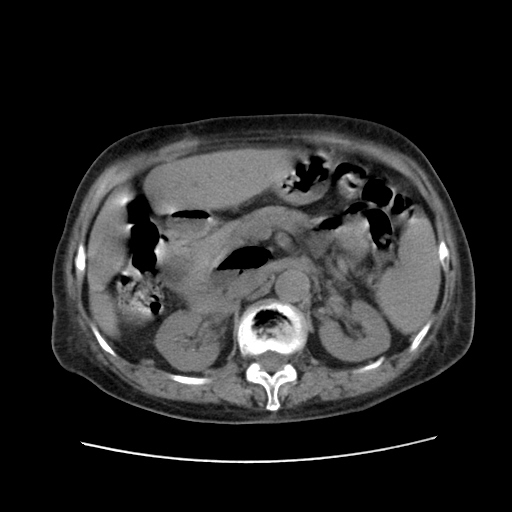

肝右叶肝内胆管结石并肝内胆管扩张。胆总管下段梗阻,考虑壶腹部占位。

肝右叶肝内胆管结石并肝内胆管扩张。胆总管下段梗阻,考虑壶腹部占位。支持